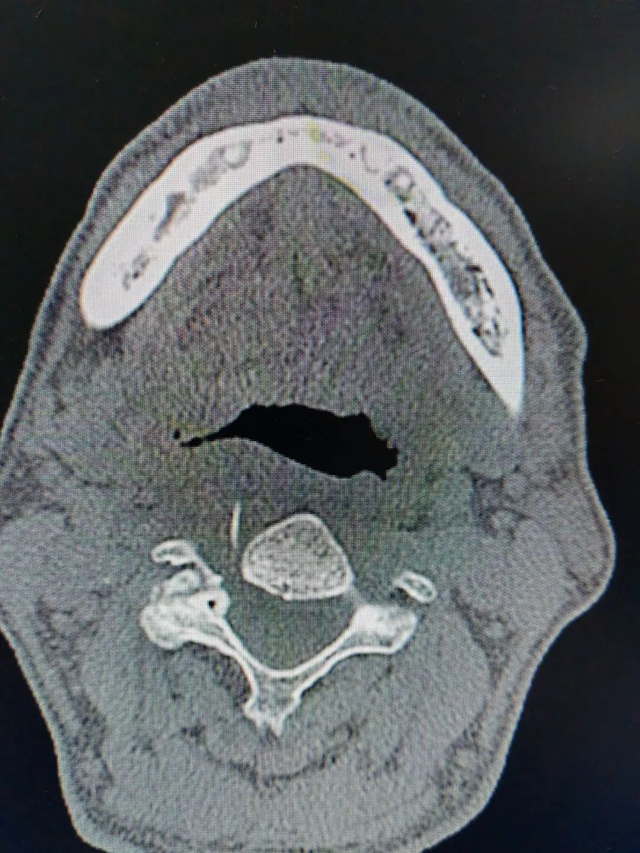

10多天过去了,刘大爷咽喉部疼痛症状越来越严重,这才来到西南医科大学附属中医医院耳鼻咽喉科就诊。王剑用喉镜为刘大爷检查发现其咽部粘膜肿胀,但没发现异物,通过咽喉部CT检查,发现咽喉右后壁软组织内有长条状异物,长约3cm。

鱼刺已经穿透刘大爷的食管,且卡了10多天,继续发展会导致局部脓肿,进而导致咽喉部水肿,影响呼吸甚至危及生命。必须及时取出,目前可采取颈外切开下咽异物探查取出术、喉镜下下咽部异物探查取出术。